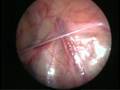

Can this operation be done laparoscopically?

Operation in hydrocele involves closing of the open passage through which the testis has come down. This can be done from outside as in open surgery or from inside by laparoscopy. With the help of laparoscopy we are able to look at the opposite side to see if the passage is open on that side as well. This can be closed at the same sitting if you wish to. Recovery from surgery, timing of surgery and discharge from hospital are the similar for open surgery and laparoscopic surgery.

Laparoscopic repairs have a slightly higher chance of recurrence as compared to open surgery. You can discuss the pros and cons in details with your doctor when you come for consultation.